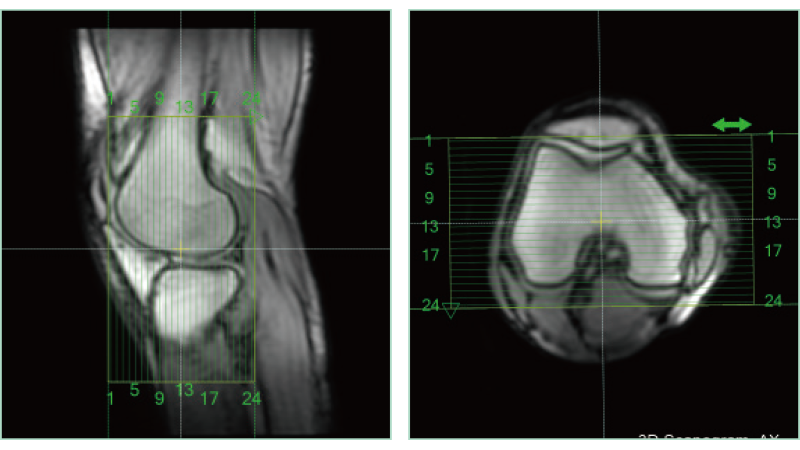

AutoPose FemalePelvis

AutoPose Knee

スライスライン設定サポート機能"AutoPose"は、Scanogram撮像終了と同時にスライスラインを設定します。